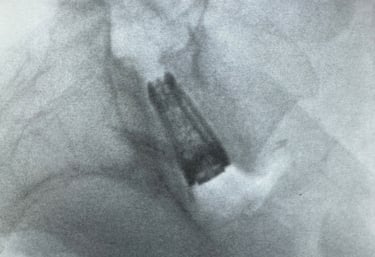

Snapshots of precision in lumbar spine imaging

Precision Imaging

Delivering clear, detailed spinal exposures.